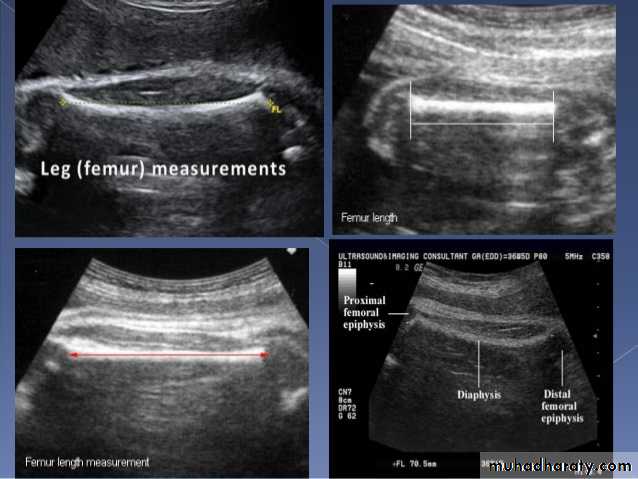

US of the obstetric & Gyne.BPD together with head circumference (HC), abdominal circumference (AC), and femur length (FL) are computed to produce an estimate of fetal weight. In the second trimester this may be extrapolated to an estimate of gestational age and an estimated due date (EDD) .